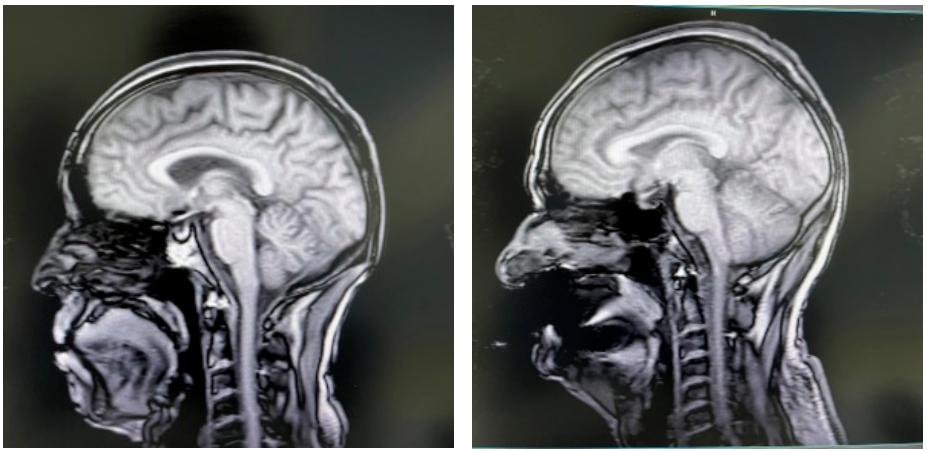

磁共振检查简称MRI,通俗讲就是在身体上施加一个强磁场,将身体里的原子核(我们的身体大约有70%都是水分,这些水分中就有很多的氢原子核)都朝向磁场方向有序排列,然后利用特定频率的电磁波进行激发,通过捕捉原子核返回原来状态所释放出的能量,形成MRI信号。

由于可以清晰显示脂肪、全身脏器、肌肉、快速流动的血液、骨骼和空气等,对脏器内部结构也能清楚显示,医生可以很好地识别病人体内的肿瘤、炎症、坏死病灶、异常物质沉着、功能阻碍、血液循环阻碍等病变,因此核磁共振对各种疾病的诊断有着非常重要的作用。

虽然核磁共振的名字中虽然带有“核”字,但它其实是没有任何核辐射的。此处的“核”是指原子核(氢质子核),不存在任何的电离辐射。由于核磁共振是磁场成像,而不是X射线,没有放射性,所以对人体无害。到目前为止,世界上还没有任何关于使用核磁共振机引起危害的报道,也未发现病人基因突变或染色体畸变的发生率有增高。

左为头部失状扫描图,右为假牙干扰后的伪影。